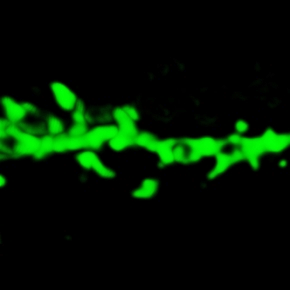

La maladie d'Alzheimer désorganise les réseaux neuronaux construits durant notre vie. Ces réseaux participent à la formation et la conservation des informations dans notre mémoire. Des chercheurs du Laboratoire de neurosciences cognitives et adaptatives (LNCA | CNRS Unistra), en collaboration avec des collègues français et indiens, viennent de caractériser des altérations épigénétiques associées aux lésions cérébrales de la maladie d'Alzheimer. A l'aide d’une molécule modifiant l'épigénome, ils ont montré qu'il était possible, dans un modèle murin de la maladie, de restaurer la mémoire et la plasticité en ciblant ces altérations. Cette étude a été publiée dans EMBO Molecular Medicine.